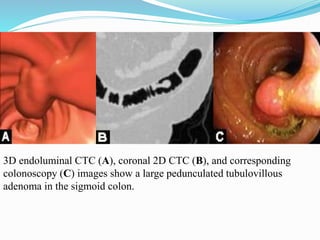

This document discusses colorectal polyps. It defines polyps and describes their types, including neoplastic and non-neoplastic polyps. It discusses adenomatous polyps in depth, noting their malignant potential increases with size over 1cm and villous architecture. Radiological diagnostic methods for polyps including single and double contrast barium enema and CT colonography are explained. The document provides an overview of polyp pathogenesis and genetic syndromes like FAP that increase cancer risk.